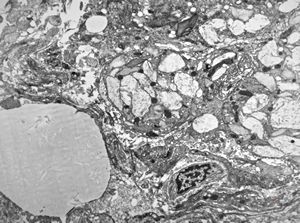

Whipple disease